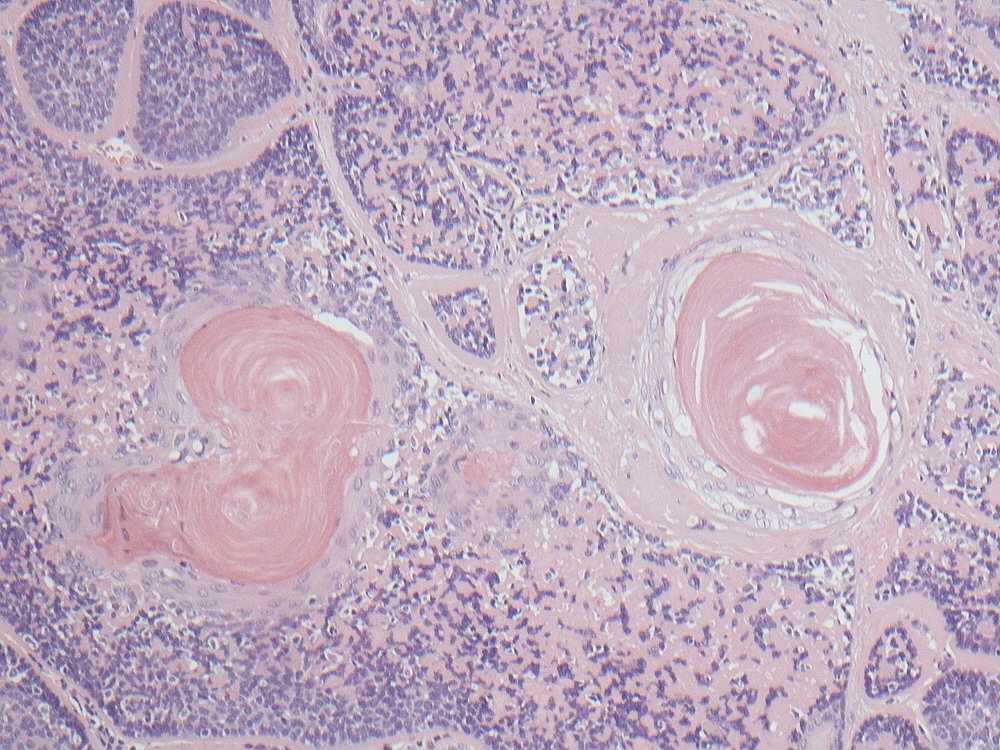

Basal cell adenocarcinoma of parotid showing jigsaw puzzle pattern, hyaline globules, focal squamous eddies and, most importantly, invasion into periglandular fat. Wide sampling essential to find those invasive foci #pathology #oralpath #entpath